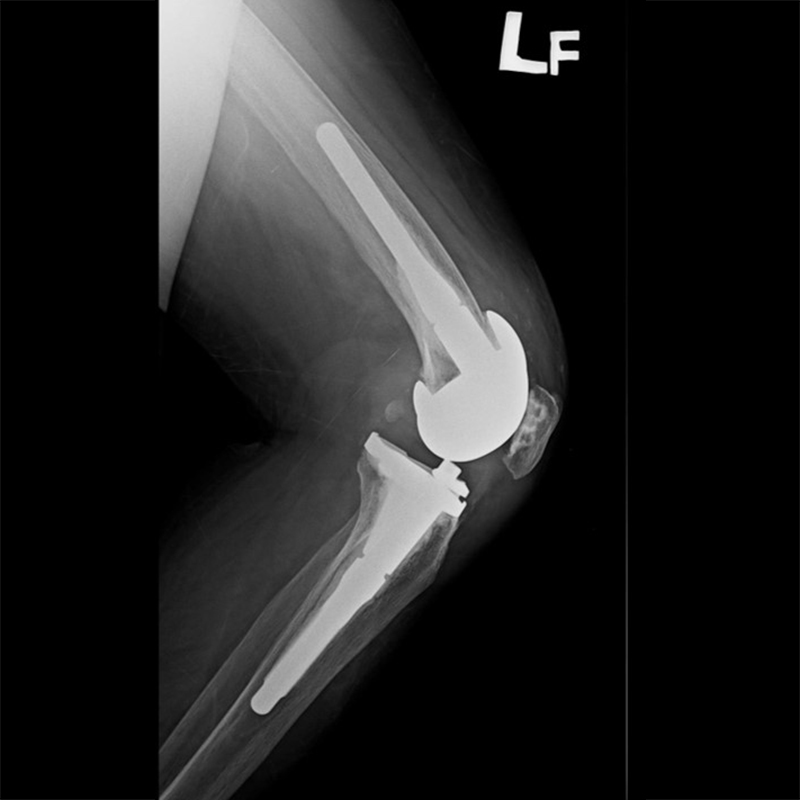

外院失敗本院再置換 首頁 案例分享 膝關節手術 外院失敗本院再置換 蕭女士 69歲 術前 術後 81歲 林女士 術前 術後 蕭女士 69歲 術前 術後 鄒女士 69歲 術前 術後 李女士 74歲 術前 術後 吳女士 71歲 術前 術後 謝女士 65歲 術前 術後